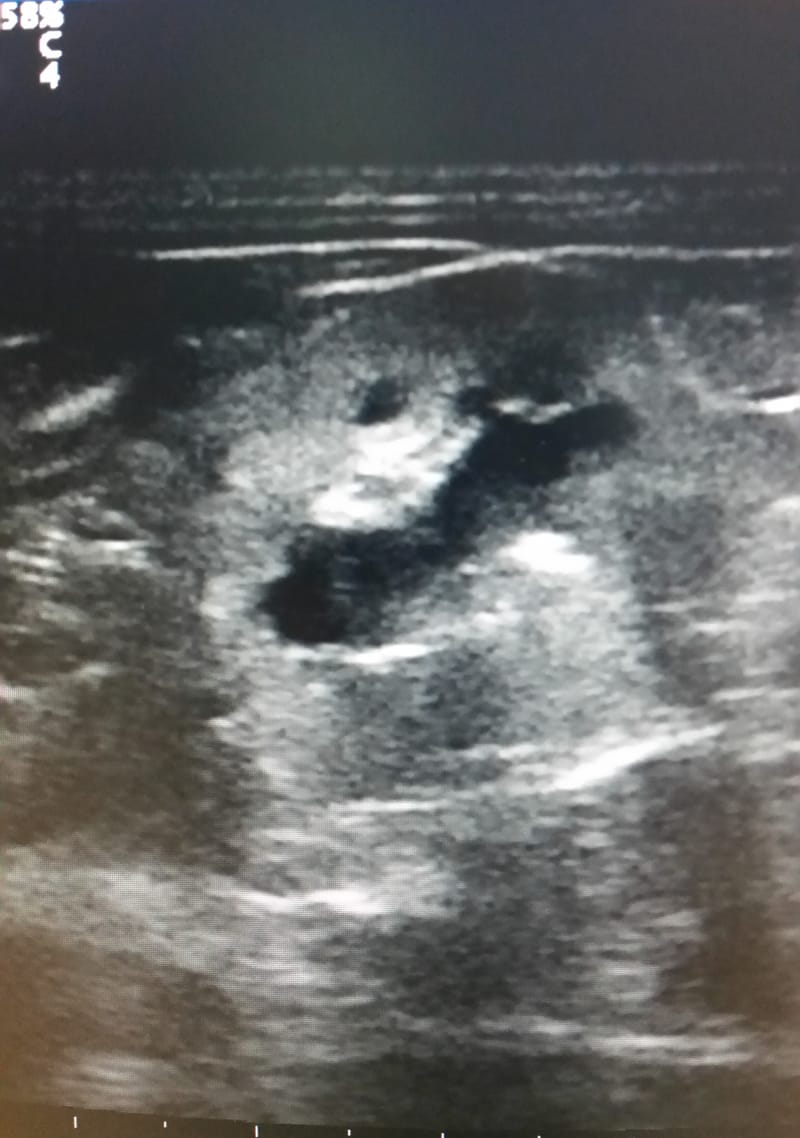

ECOGRAFIA ADDOMINALE

L'ecografia addominale rappresenta da molti anni l'indagine essenziale nell'iter diagnostico anche in medicina veterinaria. Si esegue con apparecchiature che emettendo ultrasuoni poi tramutati in immagini permettono di visualizzare gli organi interni e quindi di valutarne forma dimensioni e struttura senza arrecare alcun danno al paziente. Esame di facile attuazione ma molto influenzato dall'esperienza di chi lo esegue.